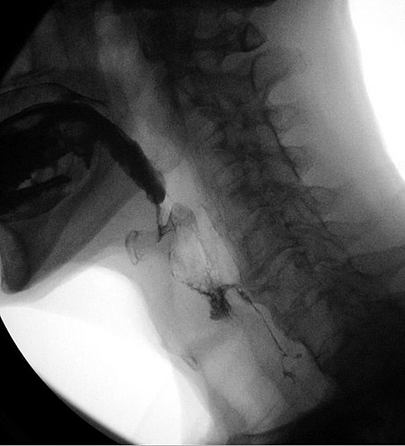

Videofluoroscopic swallow study (VFSS).

A videofluoroscopic swallow study (VFSS), also known as a modified barium swallow, is a dynamic x-ray examination of the oral cavity, pharynx and cervical esophagus. VFSS permits evaluation of the patient’s swallowing function through the administration of liquids and solids of varying consistencies to assess swallowing fluoroscopically.